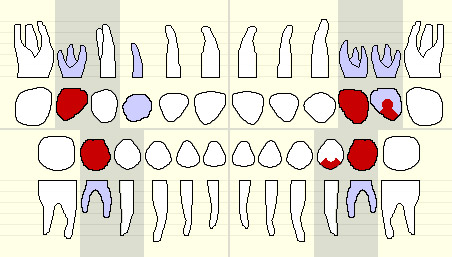

VI. Pre-Treatment Odontogram

Note: Red = caries; Blue = primary teeth; White = permanent teeth

XIX. Post-Treatment Odontogram

Note: Blue = primary teeth; White = permanent teeth; Yellow = composite; Yellow lines = fissure sealants